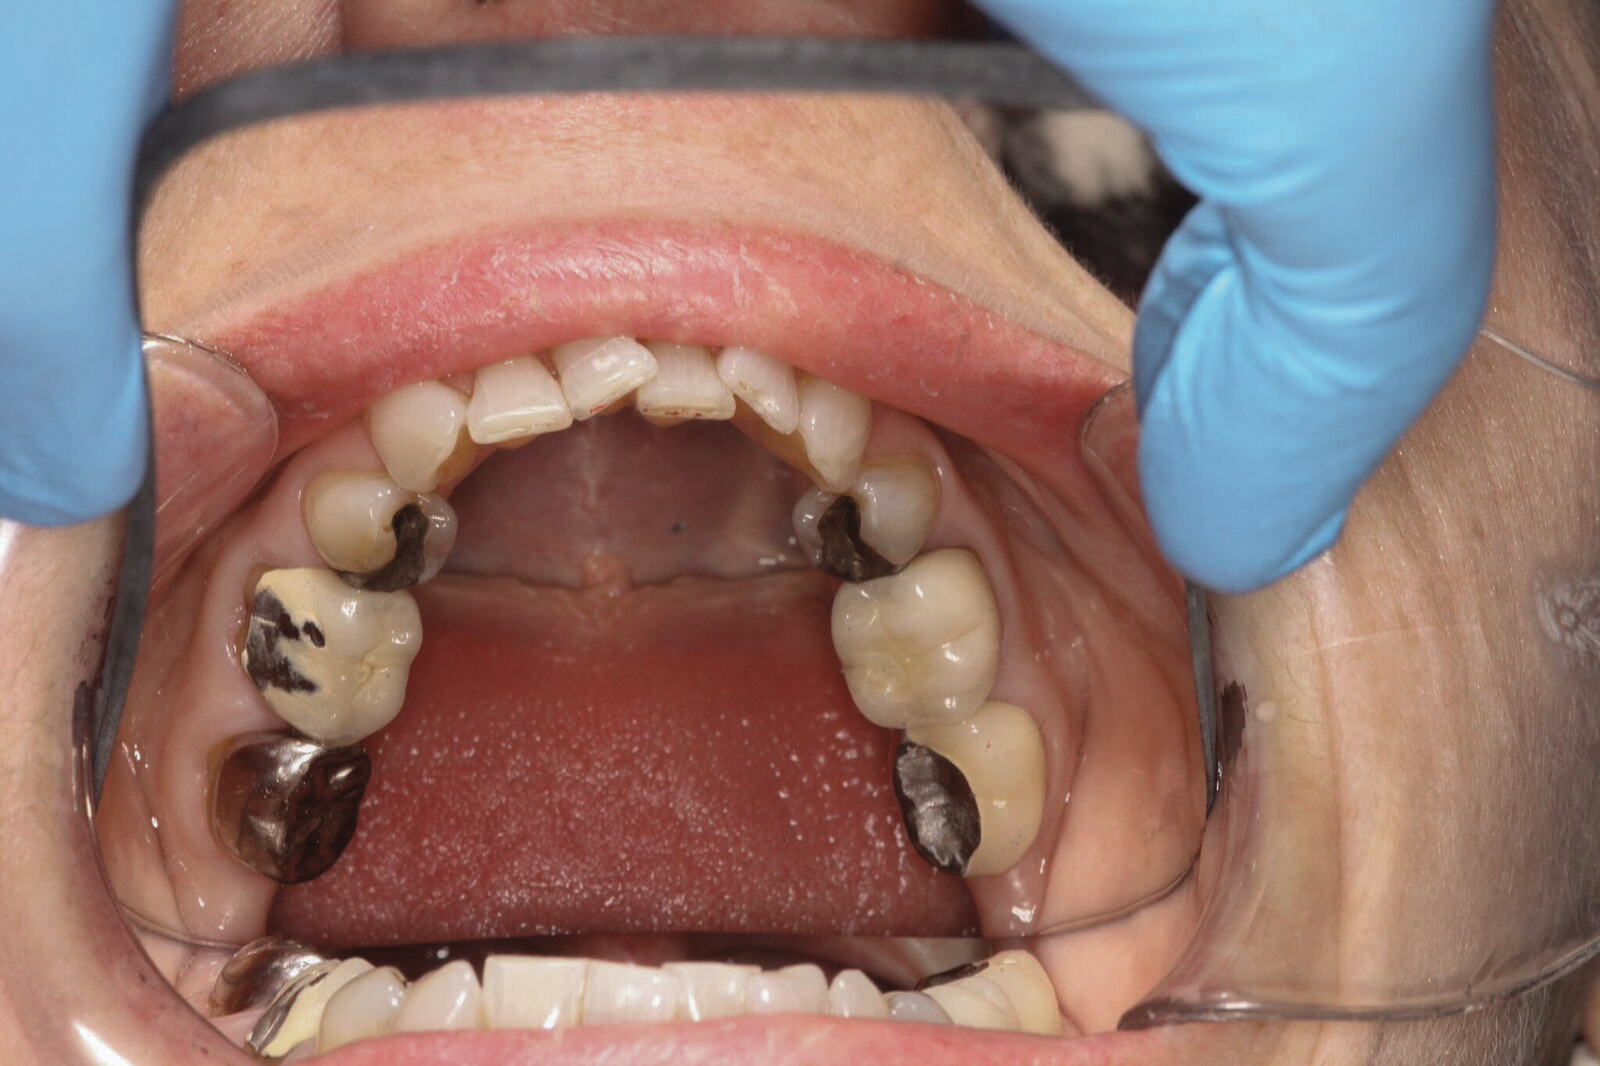

Dental sleep medicine (DSM) is a field in dentistry dedicated to the use and research of oral appliance therapy for the management of snoring and OSA. Oral appliance therapy is a noninvasive alternative to PAP therapy. Oral appliances fabricated by dentists with training in dental sleep medicine are commonly used to reposition the lower jaw forward to increase upper airway patency. Dental professionals have been recognized as being part of the multidisciplinary therapeutic team for the management of OSA because of their prime position of constant examination of the oropharyngeal areas. There are several oropharyngeal features contributing to the development of a narrow upper airway. These features are easily identifiable during a routine dental appointment, such as a large and scalloped tongue (Figure 1), narrow maxilla (Figure 2), small mandible (Figure 3), and retrognathic mandible (Figure 4). Combining clinical history intake, oropharyngeal examination, and the use of validated screening questionnaires, such as the STOP-Bang, dentists can screen for signs and symptoms of OSA and make recommendations for further diagnostic testing.

(2.) Narrow maxillary arch with deep palatal vault.

Figure 2